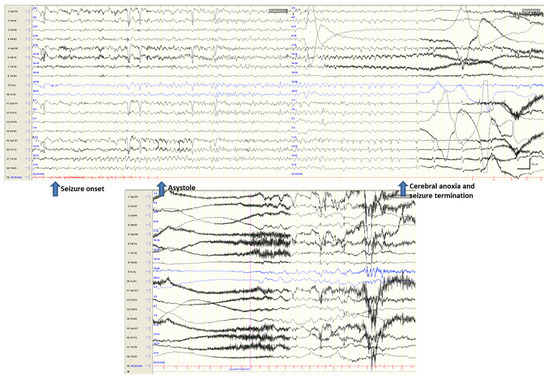

- Pasini, E.; Michelucci, R. Fit and faint or faint and fit? Clin. Neurophysiol. 2021, 132, 178–179. [Google Scholar] [CrossRef] [PubMed]